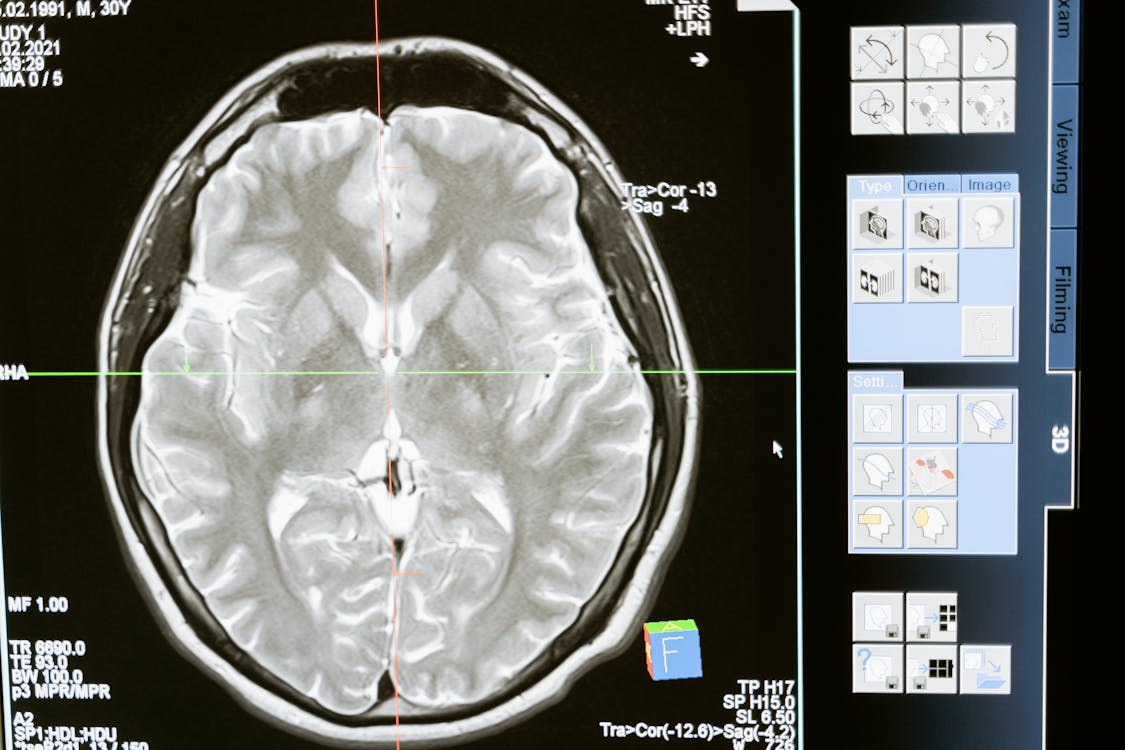

Hito científico: Descubren una «señal cerebral oculta» que predice el Alzheimer años antes del diagnóstico

Salud y Ciencia. — Un equipo de científicos de la Universidad de Brown y la Universidad Complutense de Madrid ha revelado hoy un hallazgo que podría transformar la medicina preventiva: una señal eléctrica en el cerebro capaz de predecir quién desarrollará Alzheimer con hasta dos años y medio de antelación.

Los investigadores utilizaron una técnica no invasiva llamada magnetoencefalografía (MEG) para grabar la actividad cerebral de 85 personas con deterioro cognitivo leve. Gracias a una nueva herramienta de análisis creada en Brown, llamada Spectral Events Toolbox, pudieron detectar algo que antes era invisible:

1. Es no invasivo: No requiere pinchazos ni procesos dolorosos; basta con un escaneo cerebral mientras el paciente descansa.